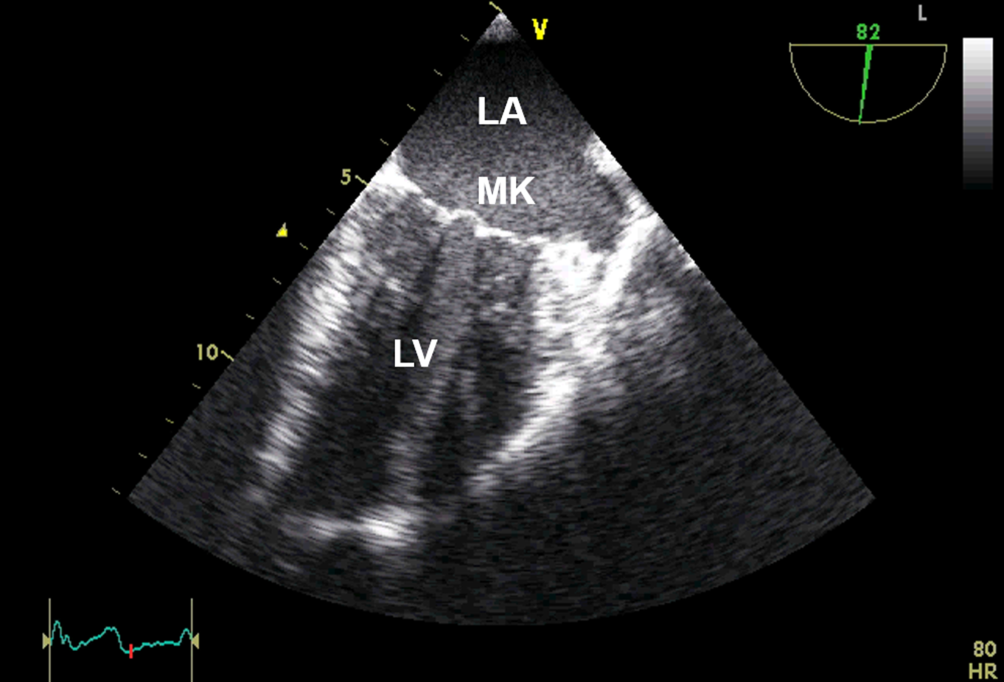

Anlotebene: 2‑Kammer-Blick

Sondenposition: mittösophageal

Rotationswinkel: 90°